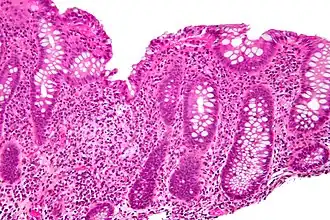

Cryptitis

In histology, cryptitis refers to inflammation of an intestinal crypt.

Cryptitis is a non-specific histopathologic finding that is seen in several conditions, e.g. inflammatory bowel disease,[1] diverticular disease,[2] radiation colitis,[3] infectious colitis.

Cryptitis. H&E stain. -